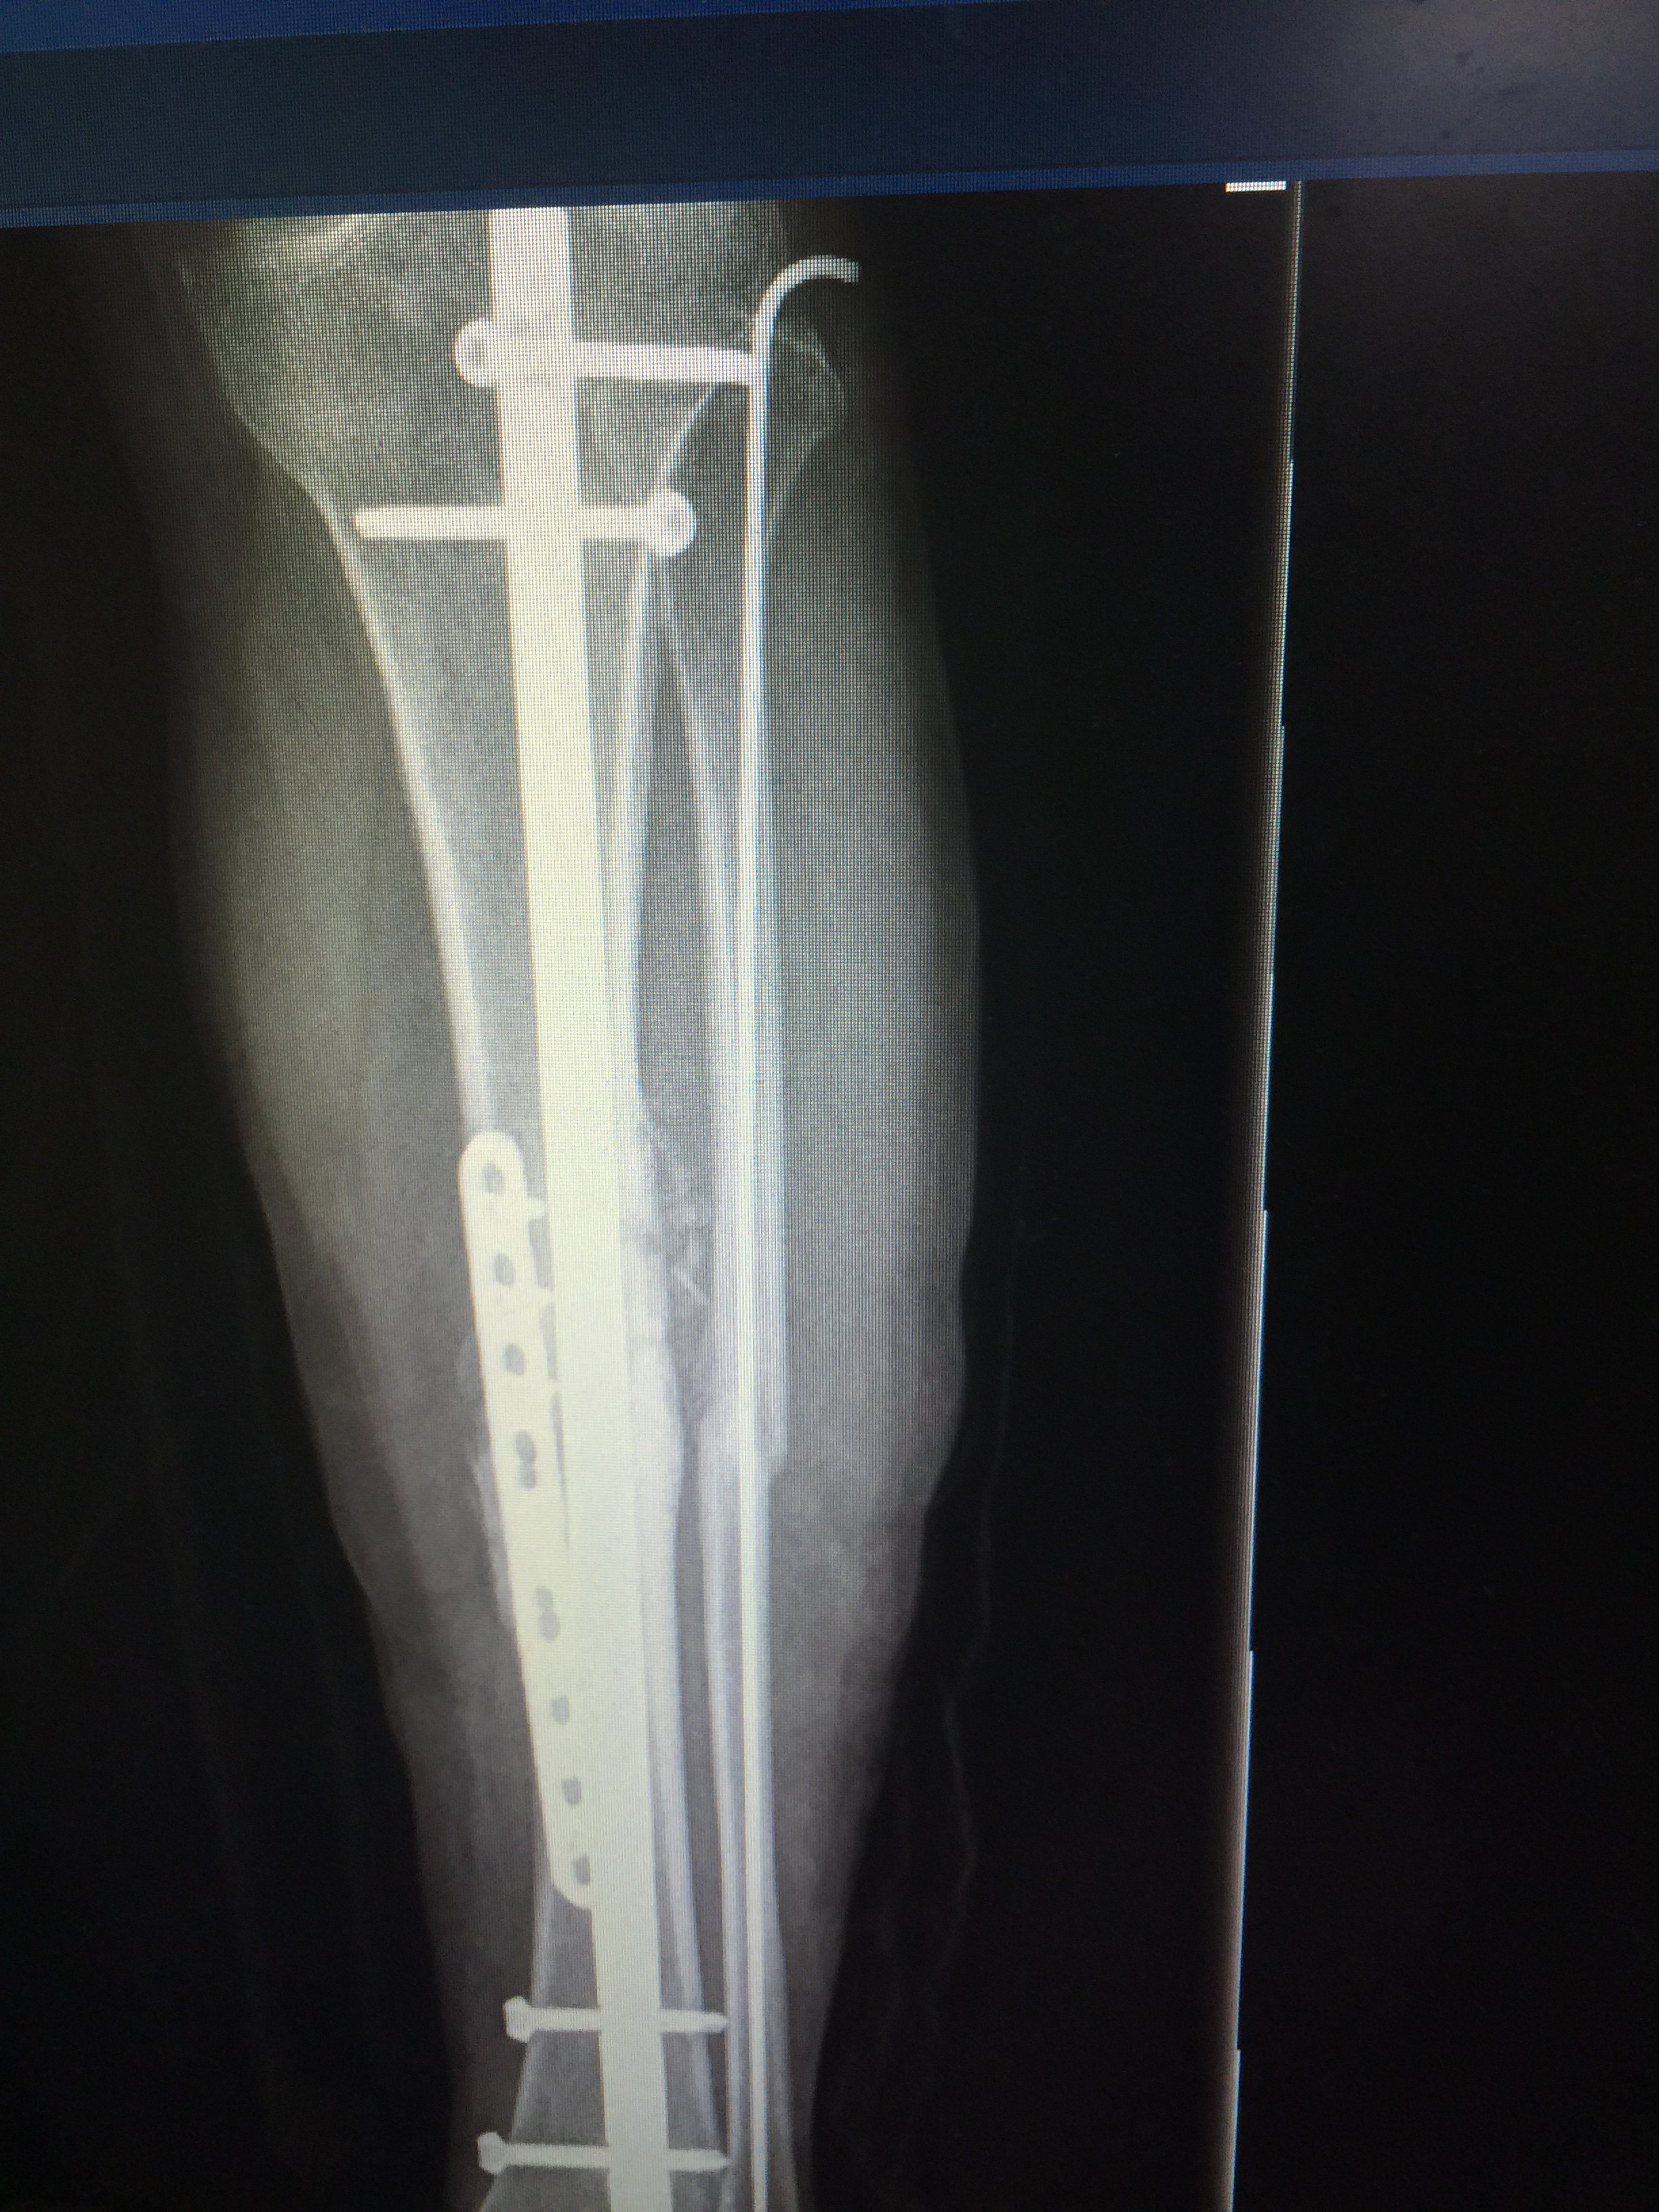

脛骨骨折 手術 プレート

医学慕课 胫骨锁定钢板外露2年骨折愈合

脛骨骨折做了內固定手術後 有什麼辦法能正常走路嗎 每日頭條

手术案例 右胫骨骨折术后感染伴骨缺损 成功案例 南京应天骨科医院

成功治愈一例胫骨骨折手术后15个月 骨不联

右胫骨下段粉碎性骨折 知乎

太原市中心医院骨科汾东一病区完成一例胫骨远端骨折髓内钉手术 微创

骨折不愈合手术后出院了

胫骨髓内钉开髓点取骨植骨治疗胫骨骨折不愈合效果良好 Medsci Cn

悟空问答 小腿胫骨断后手术后不长骨头该怎么办 4个回答